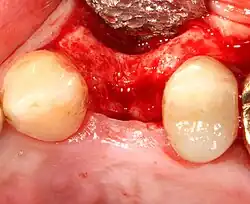

- Soft tissue reflection: An incision is made over the crest of bone, splitting the thicker attached gingiva roughly in half so that the final implant will have a thick band of tissue around it. The edges of tissue, each referred to as a flap, are pushed back to expose the bone. Flapless surgery is an alternate technique, where a small punch of tissue (the diameter of the implant) is removed for implant placement rather than raising flaps.

An increasingly common strategy to preserve bone and reduce treatment times includes the placement of a dental implant into a recent extraction site. On the one hand, it shortens treatment time and can improve aesthetics because the soft tissue envelope is preserved. On the other hand, implants may have a slightly higher rate of initial failure. Conclusions on this topic are difficult to draw, however, because few studies have compared immediate and delayed implants in a scientifically rigorous manner.[55]